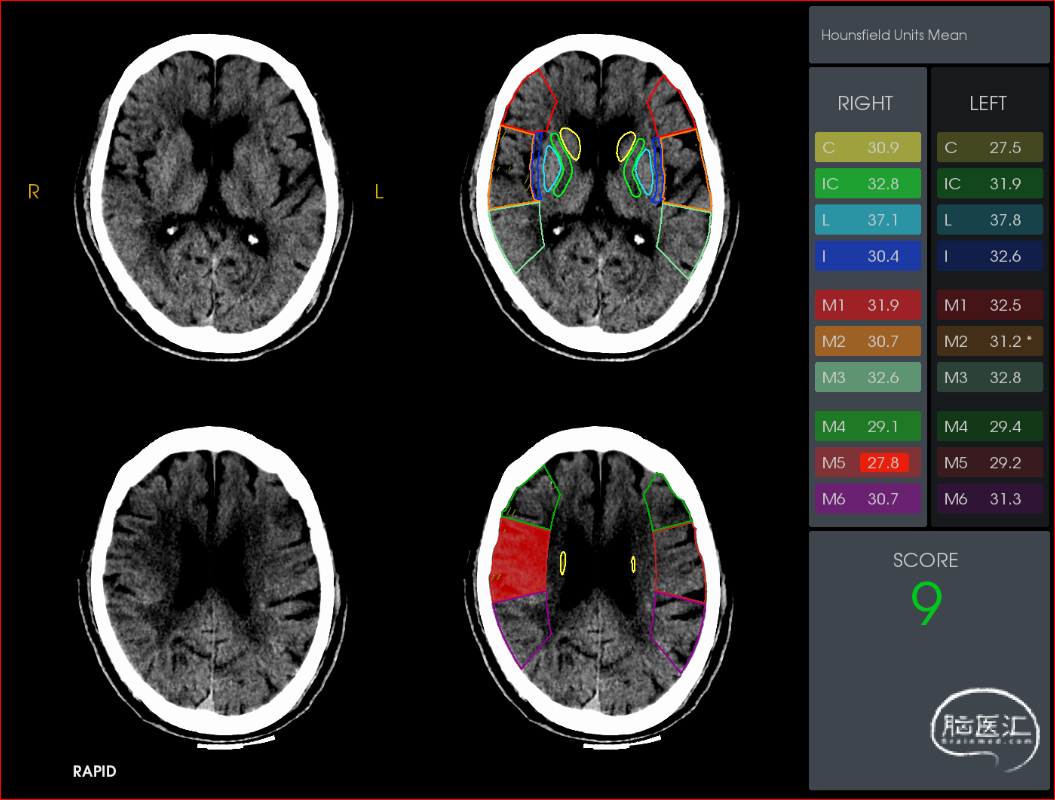

术前影像学检查结果

术前CTA可知责任血管为右侧大脑中动脉,遂在泥鳅导丝及4F多功能管的引导下,直接将8F导引导管送至右侧颈内动脉C1段,造影示右侧大脑中动脉M1远端下干闭塞,同侧大脑前动脉通过脑膜支向大脑中动脉供血区代偿供血,代偿ASTRIN分级2级,将SKATHI远端通路导管送至颈内动脉C4段,随后微导管(Rebar 18)在微导丝(Synchro 14)辅助下,小心通过大脑中动脉下干闭塞段至M2段,再将SKATHI远端通路导管顺利送至大脑中动脉闭塞段近端,并抵住血栓近端,撤出微导丝及微导管,用50ml注射器保持负压吸引抽吸导管,约1分钟后缓慢回撤中间导管至颈内动脉C4段,抽出多枚栓子,复查造影见右侧大脑中动脉各分支完全显影,TICI3级,血流速度正常。

2、多时相CTA可以清楚显示闭塞部位及血管代偿情况,可协助手术路径的判断,为手术决策提供证据。

3、CTP可为晚时间窗和时间窗不明的患者提供的组织学时间窗,可以让更多的卒中患者从血管内治疗中获益。随心所欲,管到栓除。